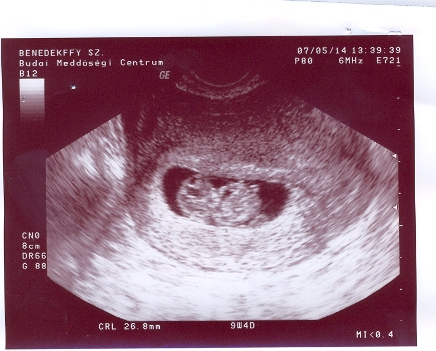

A baba:26,8mm-es B baba:25,3mm-es!Pont koruknak megfelelő!Holnap vagy este rakok fel képet!Mozgott a kezük ezerrel!Édesek voltak!

Kép Kép

Ezek az én drágáim!!!!!!